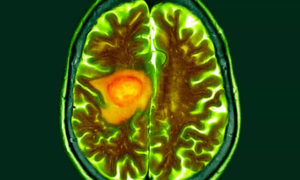

AI distinguishes glioblastoma from look-alike cancers during surgery: Study

A Harvard Medical School–led research team has developed an…